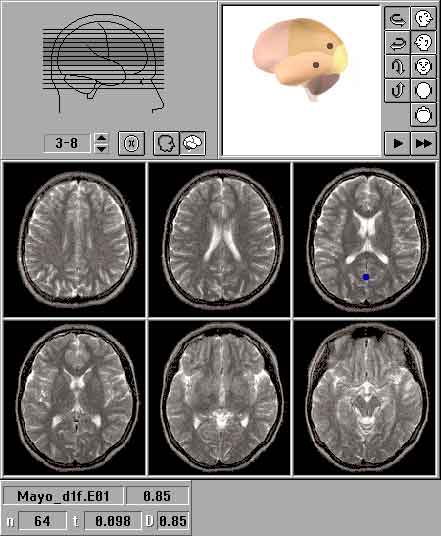

Расположение источника (генератора) ЗВП и место регистрации наибольшего значения потенциала на поверхности головы нередко не совпадали, что некоторыми авторами объясняется различной ориентацией источников ЗВП и наличием у мозга, его оболочек и ликвора свойств объемного проводника [1,2,9]. Для уточнения данных топографического картирования использовали метод трехмерной локализации дипольных источников ЗВП, предназначенный для компьютерного моделирования расположения доминирующих центров биоэлектрической активности в структурах мозга [1,2,9,16,17]. Трехмерная локализация источников ЗВП осуществлялась с помощью компьютерной программы "Брейнлок 5.0" (автор Коптелов Ю.М.). В качестве входной информации, как и для топографического картирования, использовали многоканальную запись ЗВП. Дипольные источники ЗВП изображались на ортогональных проекциях головы в виде ''стрелок'' с основанием в центре вычисленного диполя. ''Стрелки'' направлены от "минуса" диполя к его "плюсу". Также источники выводились на семь схематических изображений срезов головного мозга, сделанных в орбито-миотальной проекции. Для улучшения объемного представления источники изображались внутри трехмерной вращающейся модели головного мозга. При наличии файлов магнитно-резонансной томографии локализация проводилась с учетом реальной топографии структур мозга пациента.

Рис.2. Локализация источников вспышечных ЗВП в норме: ортогональные проекции

Рис.3. Локализация источников вспышечных ЗВП в норме: послойные изображения

Рис.4. Локализация источников вспышечных ЗВП в норме: МР-томографические изображения